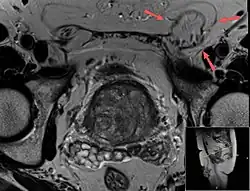

Ultrasound of an indirect hernia containing fat, with testicle seen at right.

T2 weighted MRI of the same case (done for another purpose), also demonstrating fat content.

An indirect inguinal hernia results from the failure of embryonic closure of the deep inguinal ring. In the male, it can occur after the testicle has passed through the deep inguinal ring. It is the most common cause of groin hernia. A double indirect inguinal hernia has two sacs.

When assessed by ultrasound or cross sectional imaging with CT or MRI, the major differential in diagnosing indirect inguinal hernias is differentiation from spermatic cord lipomas, as both can contain only fat and extend along the inguinal canal into the scrotum.[22]